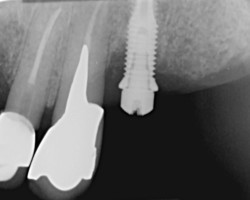

Connexion interne ou externe

Là encore, aucune étude n’a pu montrer de relations directes entre le type de connexion et le développement d’une péri-implantite cependant, les études ont montré une meilleure stabilité des connections internes et notamment des connexions pseudo cône morse limitant la perméabilité du micro-joint et donc le risque de développer une contamination au niveau du site osseux.

Bone level or Tissue level

S’il est vrai, que pour des raisons de contamination bactérienne, notamment au niveau des micro joints des implants, il est conseillé de mettre ce micro-joint à l’extérieur du niveau osseux, et que le fait d’avoir un col lisse qui place ce micro-joint au-dessus des tissus, l’adhésion des tissus à la surface titane de l’implant est très bonne.

On privilégiera donc un implant avec une connexion interne pseudo cône morse, plutôt rugueux (modéré) pour améliorer l’ostéointégration et avec un col lisse plus ou moins important pour la stabilité des tissus et positionner le micro-joint en dehors de l’os.